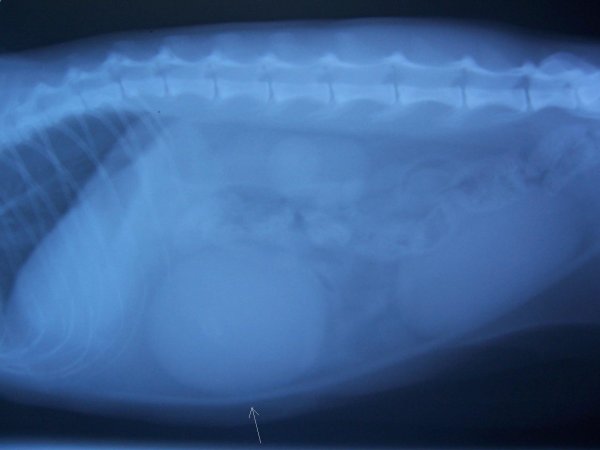

Nádor vaječníků u kočky

1.2.2017 / z našeho archivu